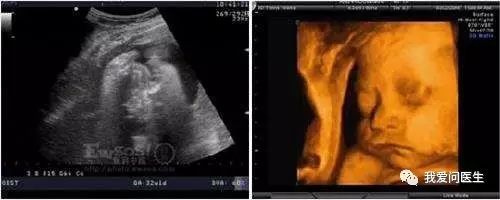

4 孕期超声一般会有六次

第三次超声检查:22-24周期间

本次检查主要为检测胎儿是否患有重大畸形,主要是筛查出胎儿致死性畸形:无脑儿、严重脑膨出、严重开放性脊柱裂、单腔心等;

第四次超声检查:28-33周期间

晚孕期胎儿畸形筛查